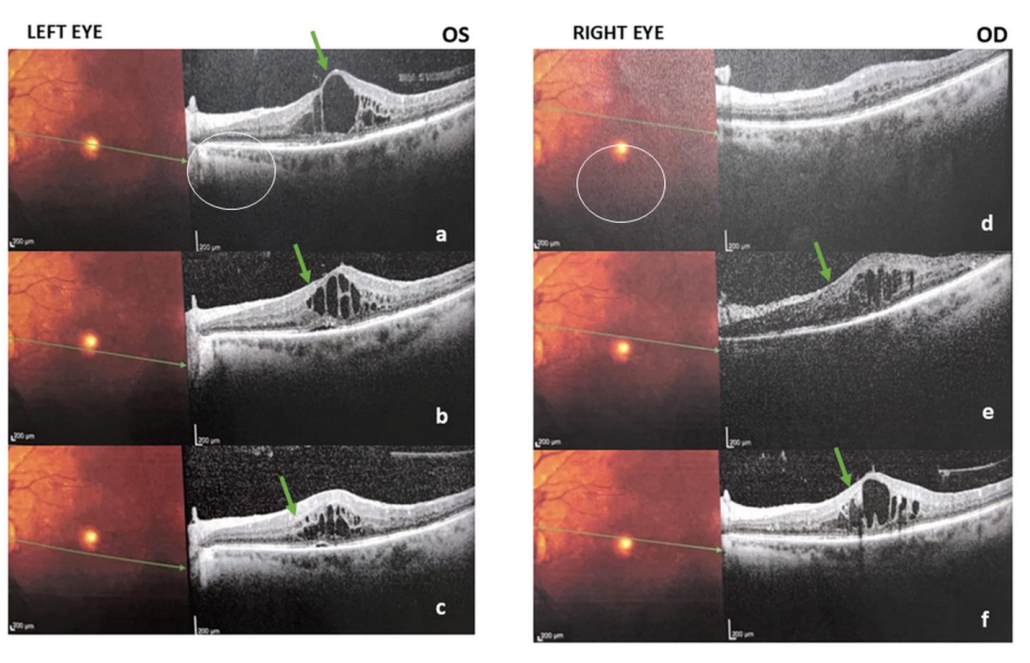

光学相干断层扫描(OCT)显示,高GV伴严重维生素D缺乏患者多见视网膜黄斑水肿、膜性增厚及渗出等病理改变,进一步支持了代谢双重压力与晚期视网膜病变的联系。